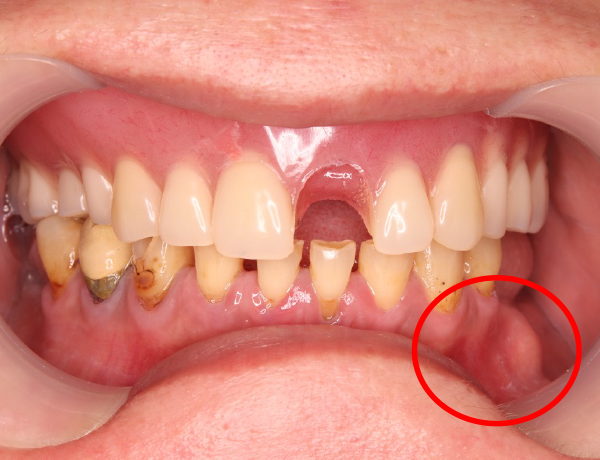

左上の歯が取れてしまっている

左上の前歯が脱落している状態が確認できます。上の噛む面から撮影した写真を見ても分かるように、入れ歯に入っていたヒビのラインが、脱落した前歯の部分まで到達していました

そのため、外から何かが強くぶつかって前歯が取れたのではなく、ヒビが進行して内部で「地割れ」のような状態が生じ、最終的に前歯が自然に脱落したと考えられます。

正面観

左下に入れ歯が入っておらず歯がないので、噛み合わせは左右アンバランスになってますね。赤丸の部分は、骨隆起ですね!噛み合わせの強い方に現れる骨の隆起になります。